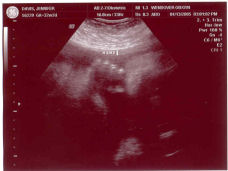

New Ultrasound

We went for another ultrasound today. They checked out the baby girl and she is fine. She weighs 4 lbs. 7 oz. and is the 50% percentile for weight. You can't get more normal than that. Her brain and major organ measurements were also all normal. They tried to get a good picture of her face to do a 3d, but she was being very shy. The best picture we got (i.e. you can tell what it is) was of her hand. Here it is: